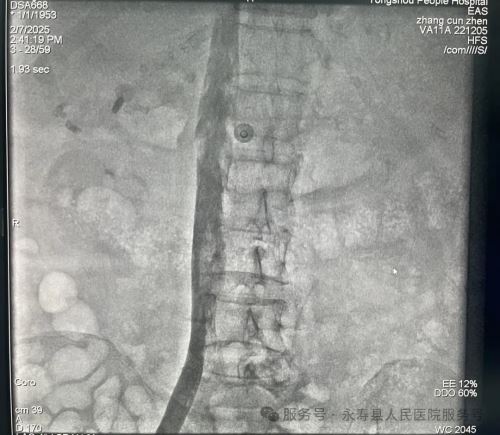

手术在上级医院专家的协助及介入科团队辅助下进行,为患者行下腔静脉滤器植入术,经股静脉植入鞘管。造影下腔静脉无血栓形成,肺动脉造影显示右上肺动脉(小动脉)中远段肺栓塞形成,肺栓塞诊断明确,是下腔静脉滤器植入绝对适应症,确定滤器的适宜型号和释放系统后,在肾静脉下端置入下腔静脉滤器,并确认其位置完好。整个手术过程历时仅30分钟,患者无不适反应,经后续治疗效果良好。

下腔静脉造影